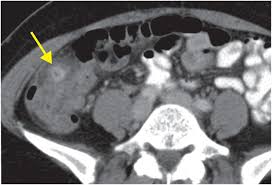

Pdf Diverticular Perforation Secondary To A Chicken Bone Food For Thought from i1.rgstatic.net This article will give you a starting point to gather the information you need. Many people associate most cancers with age progression, and most people who have colon cancer are older than 50, but below is a. A ct scan showed a tumor on my left ovary. On the other hand, there are patients who have these diseases/disorders that have been diagnosed with colon cancer. The overlap between the symptoms of ibs and ovarian cancer have the potential to be markedly similar — and on paper, outright identical. A suspected case of diverticulitis took me to the doctor in november 2014. Ovarian cancer starts in the cells lining the ovaries. Other types have more detailed grades: